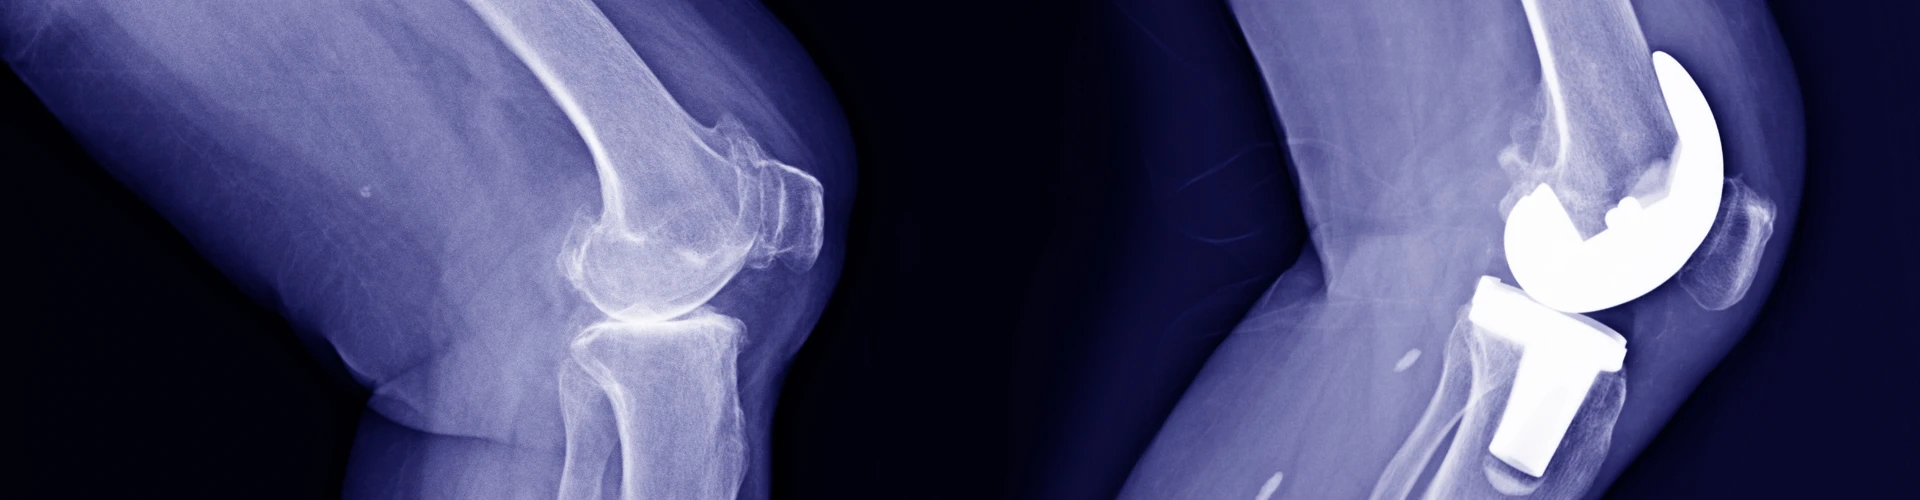

Arthroplasty

Arthroplasty, also known as joint replacement, is a surgical procedure aimed at replacing a damaged joint with an artificial joint made from metal, ceramic, or plastic materials. Typically, healthcare professionals opt for a total joint replacement, where the entire joint is replaced. However, in some cases, only the damaged portion of the joint is replaced. The most frequently replaced joints are hips, knees, and shoulders.